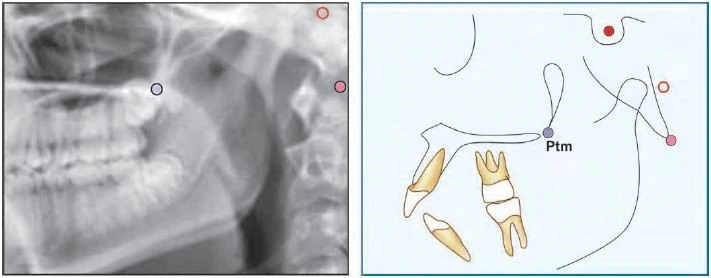

Pterygomaxillary Fissure (Ptm) Có một hình ảnh có hình giọt nước, bóng phía trước là mặt sau của lồi cùng xương hàm trên. Điểm Ptm là giao của biên giới phía dưới của lỗ tròn với thành sau của khe chân bướm hàm.